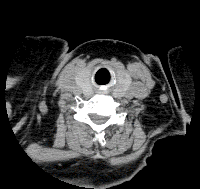

CT画像の例

頚部CT水平断 胸部CT冠状断(縦隔条件) 胸部CT冠状断(肺野条件)